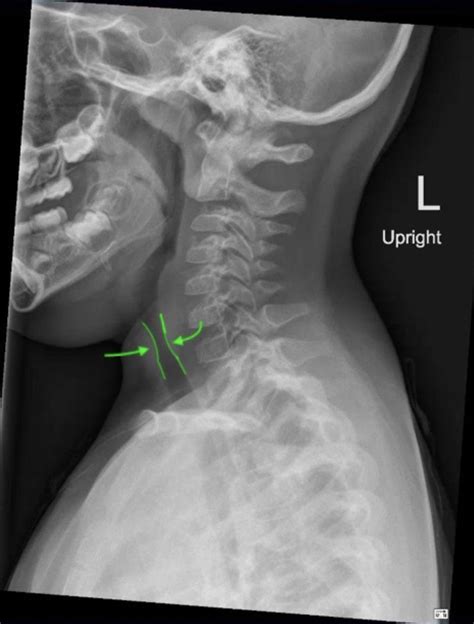

The Steeple Sign Croup is a specific finding observed on a frontal chest or neck X-ray. When a child with suspected croup undergoes imaging to rule out other, more serious causes of airway obstruction, radiologists look at the column of air within the trachea.

Normally, the trachea appears relatively straight on an X-ray. However, in cases of significant subglottic inflammation (swelling just below the vocal cords), the air column becomes narrowed. On the X-ray, this narrowing creates a shape that resembles the sharp, pointed roof of a church steeple, hence the name Steeple Sign.

A physician might order an X-ray to search for the Steeple Sign Croup in specific scenarios where they need to rule out other potential causes of airway distress, which can mimic the symptoms of croup. These conditions may include:

• Epiglottitis: A rare but medical emergency involving severe swelling of the epiglottis.